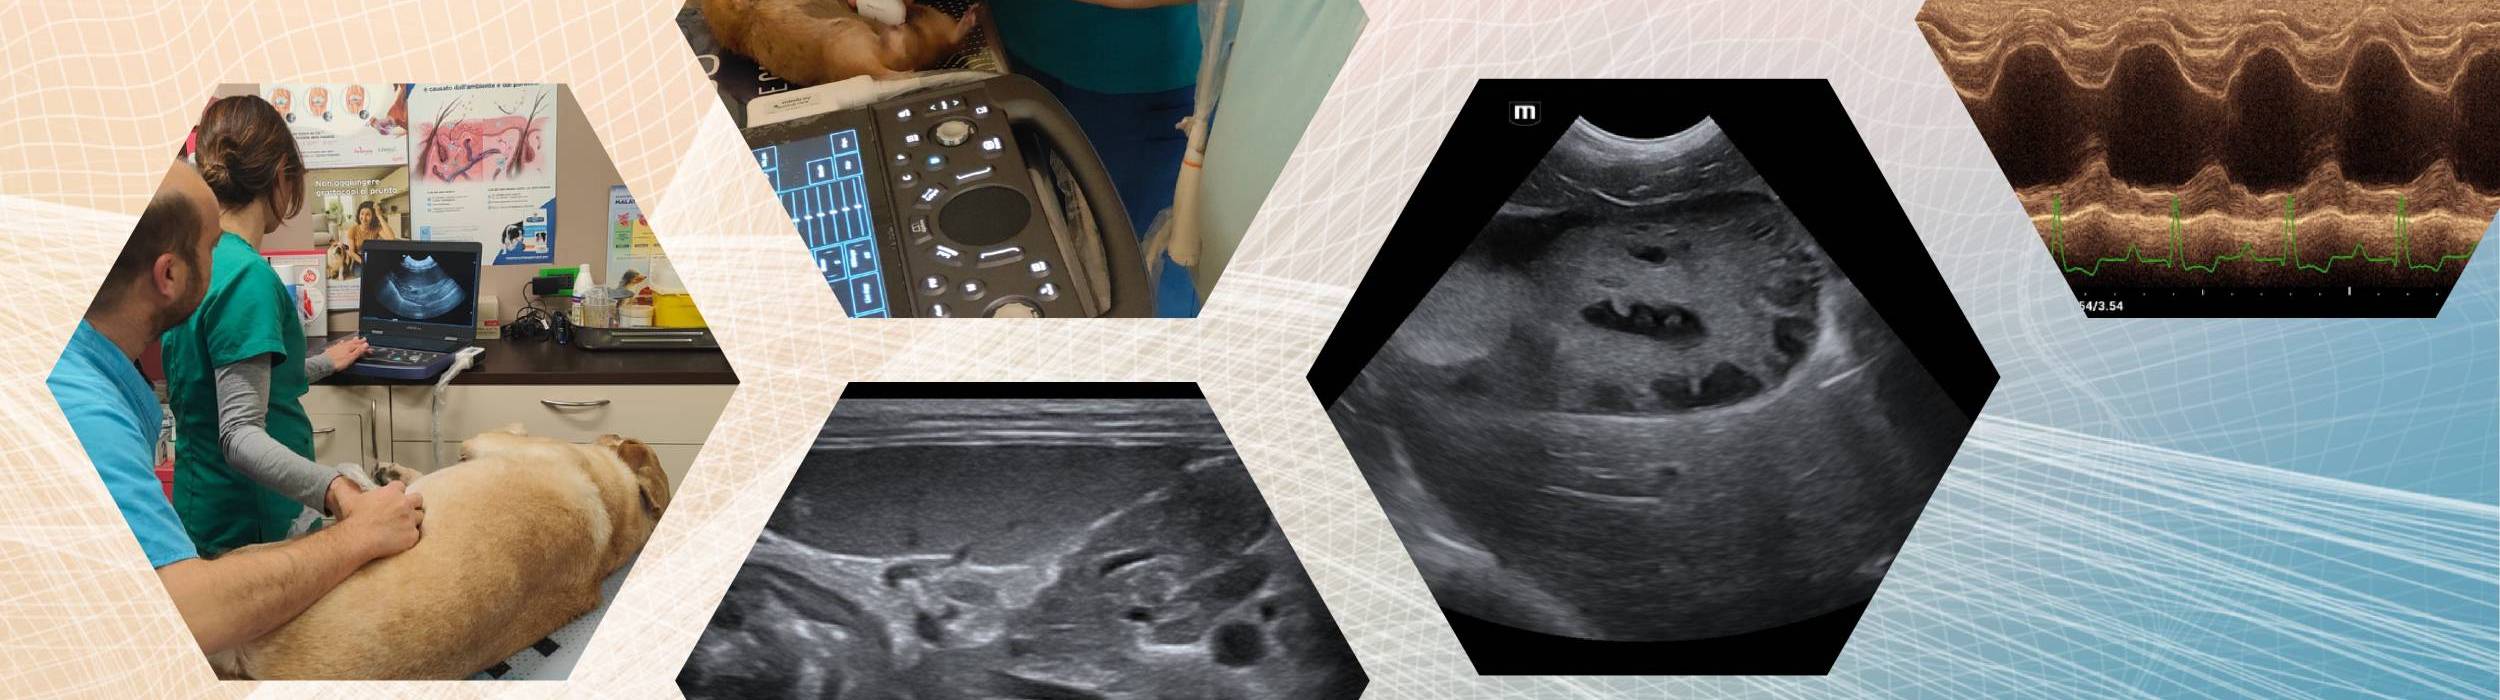

Un percorso formativo intensivo e altamente personalizzato, pensato per offrire un’esperienza didattica esclusiva in rapporto diretto 1:1 tra professionista e discente oppure tra professionista e struttura veterinaria richiedente.

Lo stage si svolge generalmente nell’arco di una o due giornate complete, con un’impostazione prevalentemente pratica e orientata alla realtà clinica quotidiana.

Formazione individuale dedicata al singolo veterinario, con affiancamento diretto durante l’attività ecografica o ecocardiografica.

Sessione formativa erogata direttamente presso la clinica richiedente, con focus sull’ottimizzazione dei protocolli diagnostici, del flusso di lavoro e dell’utilizzo della strumentazione disponibile.

• Ecografia addominale

• Ecografia internistica avanzata

• Ecografia interventistica

• Ecocardiografia di base o avanzata

• Approccio integrato clinico–ecografico